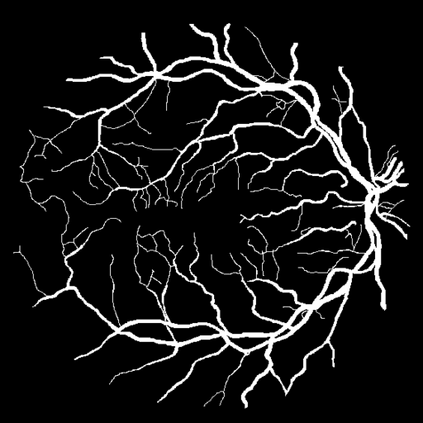

Vessel segmentation is an essential task in many clinical applications. Although supervised methods have achieved state-of-art performance, acquiring expert annotation is laborious and mostly limited for two-dimensional datasets with a small sample size. On the contrary, unsupervised methods rely on handcrafted features to detect tube-like structures such as vessels. However, those methods require complex pipelines involving several hyper-parameters and design choices rendering the procedure sensitive, dataset-specific, and not generalizable. We propose a self-supervised method with a limited number of hyper-parameters that is generalizable across modalities. Our method uses tube-like structure properties, such as connectivity, profile consistency, and bifurcation, to introduce inductive bias into a learning algorithm. To model those properties, we generate a vector field that we refer to as a flow. Our experiments on various public datasets in 2D and 3D show that our method performs better than unsupervised methods while learning useful transferable features from unlabeled data. Unlike generic self-supervised methods, the learned features learn vessel-relevant features that are transferable for supervised approaches, which is essential when the number of annotated data is limited.